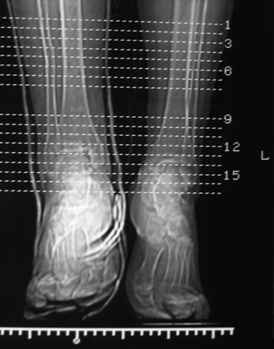

Остеопороз (продолжение 3) - данные КТ

Продолжая тему представляю данные КТ нашей пациентки.